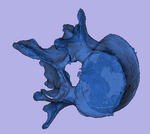

This dataset contains 3D modls obtained from in vitro CT of a human vertibral body segment (L4) before and after regional damage. Goal is to align the two models to study in detail the local changes that occurred and obtain estimates of structural integrity loss. Because the two orientations differ widely between acquisitions image-to-image registration has reduced robustness due to difficulty in initializing a good starting condition. Surface registration on the other hand is very robust toward strong difference in pose and he ce makes a good candidate for obtaining a fully automated first alignment.

5. Surface Registration

1. Note that Surface Registration on Slicer version 3.6.3 on some platforms may not operate properly (as of Aug. 2011). Slicer v.3.6.4 is recommended

2. go to Surface Registration] module

3. Landmark transform node: select Rigid

4. Max. number of iterations: increase to 150

5. max. number of landmarks: increase to 500

6. check box for start by matching centroids

7. Input Surface: select "defect_model"

8. Target Surface: select "intact_model"

9. Output Transform: select "New Transform", rename to "Xf1_defect-to-intact_Rigid" or similar

10. click Apply